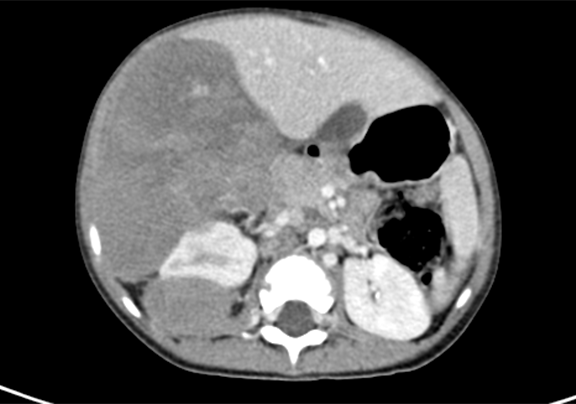

上腹部增强CT示:肝右后叶-右肾上腺区-右肾上极区域占位,考虑恶性肿瘤,肝母细胞瘤?并腹膜后转移。

将0.625mm双源薄层CT资料的静脉期和动脉期Dicom格式文件导入海信CAS系统。

通过调节窗宽窗位调整CT序号,对肿瘤,肝实质,胆囊,下腔静脉,肿瘤,肝动脉、门静脉及肝静脉等进行三维重建;系统自动计算肿瘤体积和肝脏体积。

模拟手术操作,自动计算切除肿瘤体积。肝脏体积为660.9ml,肿瘤体积为812.3ml,肿瘤体积为肝脏体积的122.9%,通过比对3-4岁正常肝脏体积为522.63±121.24 ml,肿瘤所占比例较大,且包裹右侧肾脏、及腹腔大血管,手术无法完整切除肿物,不建议给予手术治疗。

术前CT检查:

动脉期

静脉期

平衡期